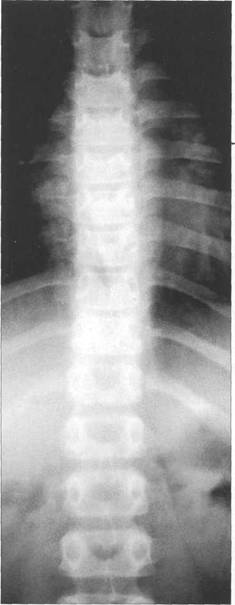

реть взаимное расположение этих линий. Смещений тел позвонков при функциональных про

ThXI_xn, Thx